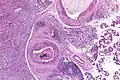

Their histologic appearance is similar to ductal breast carcinoma.

Intermed. mag.